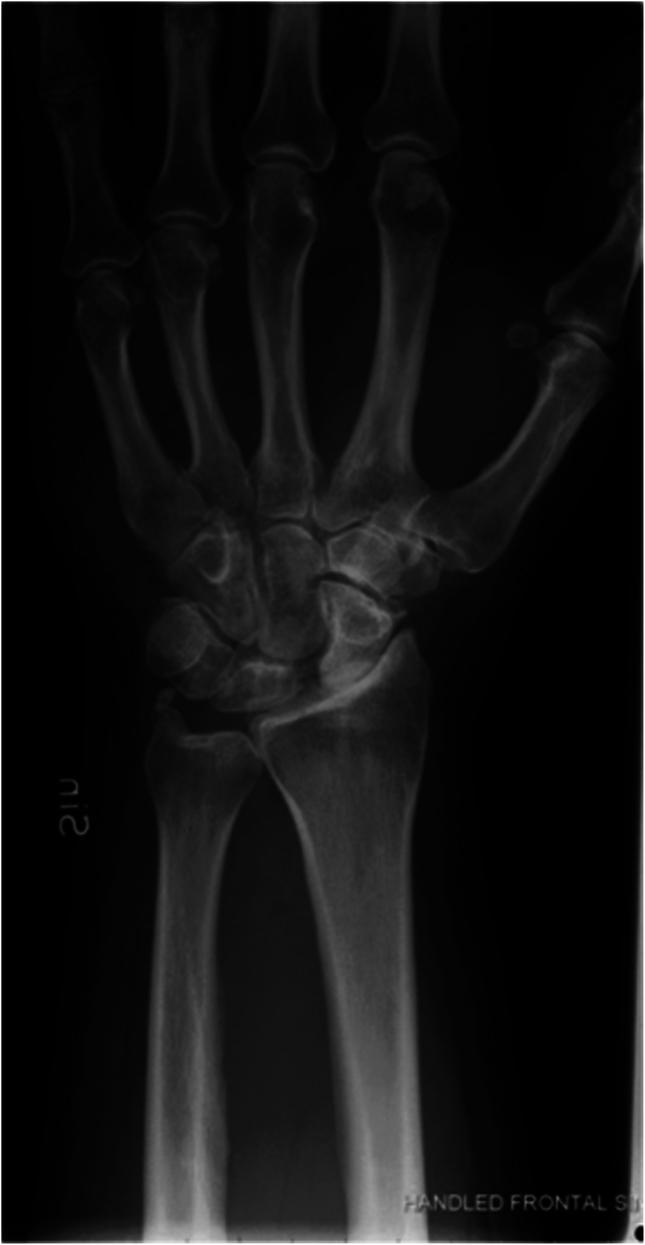

Injuries to the scapholunate interosseous ligament (SLIL) complex can result in a predictable cascade of incongruous motion in the carpus that leads to radiocarpal degeneration. Both acute traumatic impact and repetitive motion can render the SLIL insufficient. A thorough understanding of SLIL anatomy is required for appropriate diagnosis and treatment. Here, we review scapholunate ligament anatomy, prevention strategies, methods of diagnosis, nonoperative and operative treatments, and outcomes. A myriad of treatment options exist for each stage of the SLIL injury, and management should be an open discussion between the patient and physician.

舟月骨间韧带(SLIL)复合体损伤可导致腕骨出现一系列可预测的不协调运动,进而导致桡腕关节退变。急性创伤性撞击和重复性运动均可致使SLIL功能不全。为了进行恰当的诊断和治疗,需要对SLIL的解剖结构有透彻的了解。在此,我们回顾舟月韧带的解剖结构、预防策略、诊断方法、非手术及手术治疗方法以及治疗效果。对于SLIL损伤的每个阶段都有众多治疗选择,治疗方案应是患者与医生之间的充分讨论。